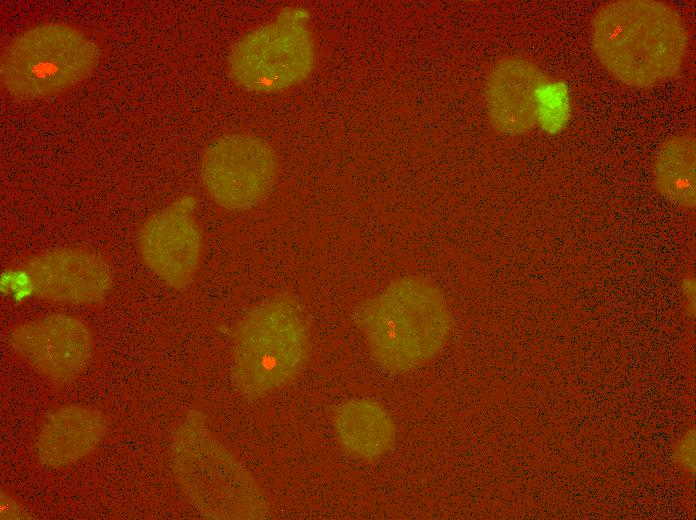

Overlay

Overlay with DAPI